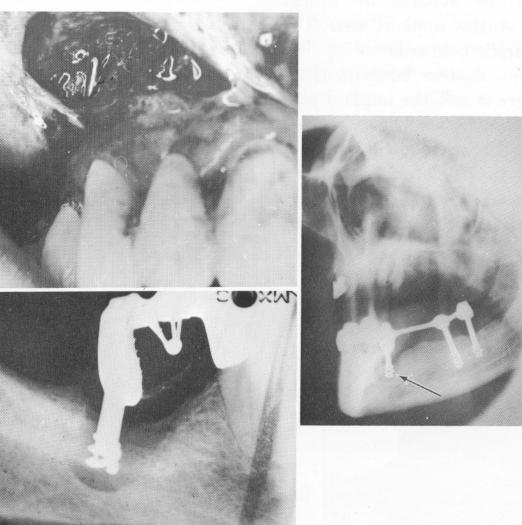

Fig. 14-4. A, A pin implant perforating the labial plate of bone is seen by incising and retracting the mucoperiosteal tissue. B, Post type implants must not be placed into recent sockets unless they can be set beyond the floor of the socket into a deeper artificial one and immediately stabilized with a prefabricated fixed denture. Otherwise a rapid epithelial invagination takes place directly into the sockets, preventing future bone regeneration. (From Linkow, L. I.: Alloplastic implants. In Goldman, H. M., Forrest, S. P., Byrd, D. L., and Mc-Donald, R. E.: Current therapy in dentistry, vol. 3, St. Louis, 1968, The C. V. Mosby Co., pp. 335-356.) C, Another post type implant failing in an open socket. If no bone in the floor or the walls of the socket is available for some part of an implant, the intervention should be delayed until the bone heals.

1 Labial plate perforation by pin seen after retracting mucoperiosteum